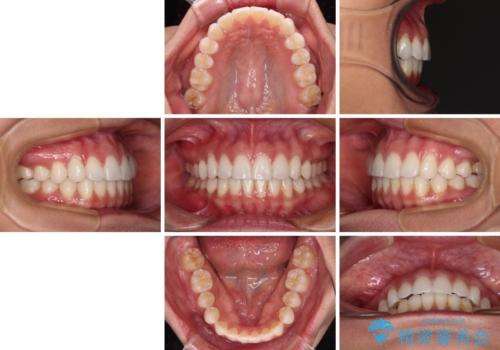

- 前に出ている上顎前歯が気になるとのことで来院された患者様です。

インビザラインを用い、IPR(歯と歯の間を削る)と歯列全体を後方に移動させることで、可能な限り前歯の突出感を改善することとしました。

元々の歯列も整っており、横顔の印象の出っ歯ではなかったため、仕上がりに満足できない可能性があると心配しておりましたが、口が閉じやすくなり、患者様には大変満足していただきました。